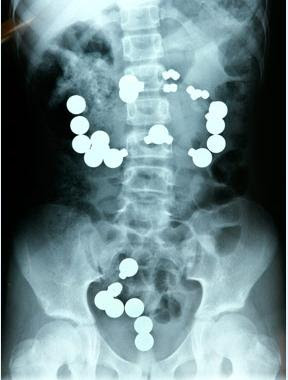

Ini adalah gambar sinar-x selangkangan juara Tour de-France, lance armstrong.